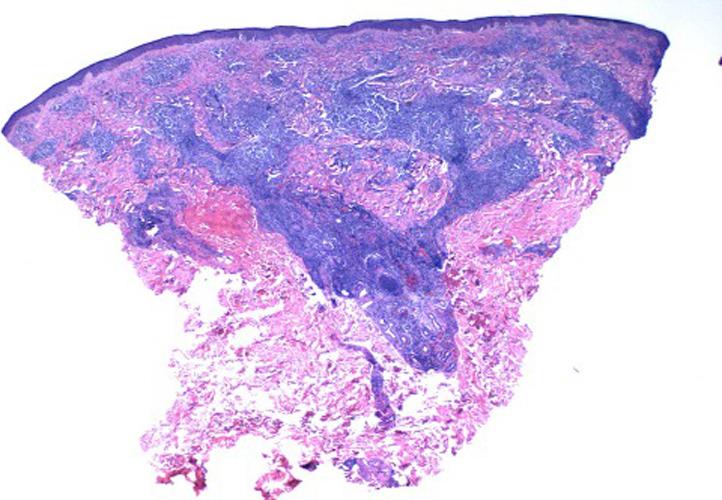

A case of secondary syphilis masquerading as cutaneous lymphoma.

JAAD Case Rep. 2021 Jun 9;14:17-20. doi: 10.1016/j.jdcr.2021.05.036. eCollection 2021 Aug.